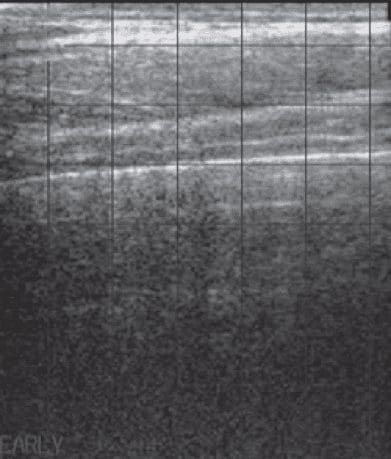

正常肺内空气的存在会阻止超声波深入肺实质。因此,与充气肺接触的高反射性胸膜表面。在超声上很容易识别为与呼吸同步移动的均匀高回声线。下图显示了没有肺部疾病证据的正常奶牛的肺表面。

正常犊牛肺部超声图像